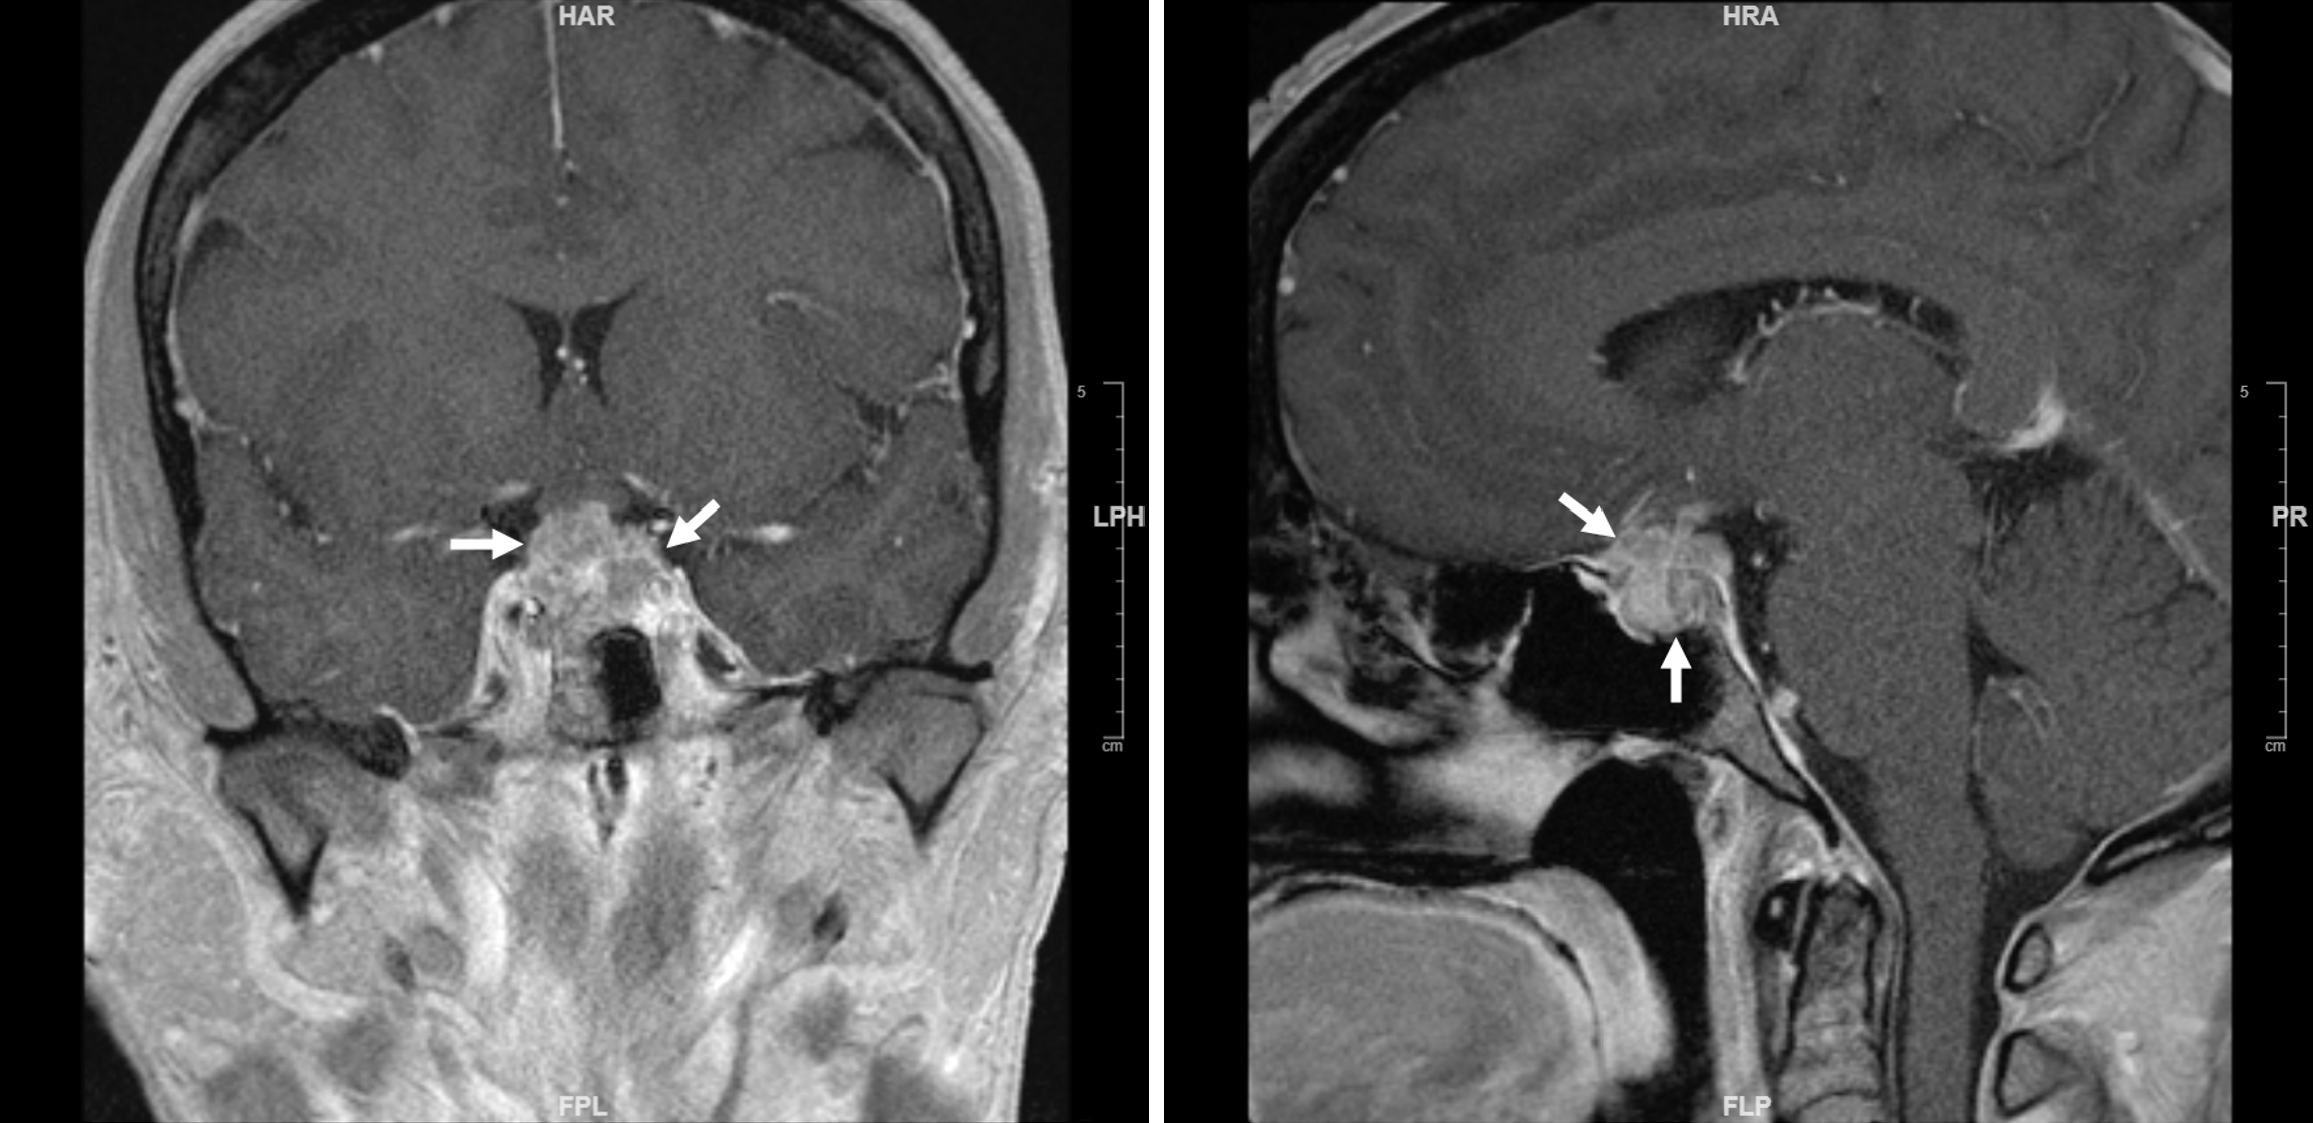

Figure 1 Pituitary magnetic resonance imaging of a patient with sellar atypical teratoid/rhabdoid tumor.

Left, coronal view; right, sagittal view. Note the extensive bilateral cavernous sinus invasion and optic chiasm displacement. Arrows: Tumor. Reproduced from Yu[14]. Citation: Yu R. Sellar Mass in 2 Patients With Acute-Onset Headache and Visual Symptoms: Not Your Usual Pituitary Adenoma. AACE Clin Case Rep 2023; 9: 197-200. Copyright © 2015 Elsevier Inc. Published by Elsevier Inc. This is an open access article with User License: Creative Commons Attribution-NonCommercial-NoDerivs (CC BY-NC-ND 4.0). See: https://creativecommons.org/licenses/by-nc-nd/4.0/.